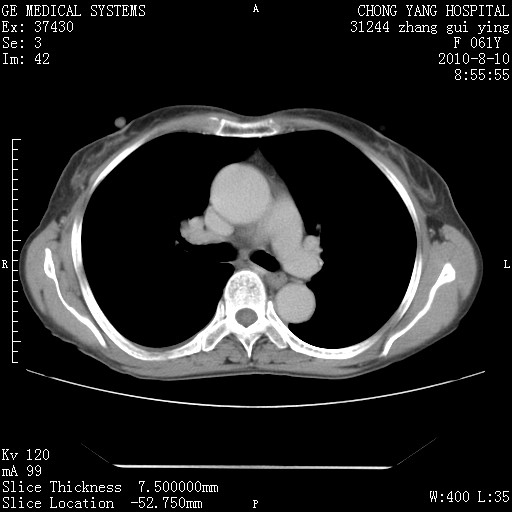

标题: CT28314:F61Y胸部增强,发热咳嗽一周入院,后面的为一周前平 [打印本页]

标题: CT28314:F61Y胸部增强,发热咳嗽一周入院,后面的为一周前平

1、支持考虑右侧中央型肺癌伴右肺中叶节段性不张及下叶支气管黏液痰栓    2、左肺上叶舌段感染。

支持3楼意见,还要考虑:纵隔及肺门淋巴结转移、右侧少量胸腔积液。

确切的说:1:右肺下叶中心型肺癌侵及中叶支气管并中叶不张,纵膈淋巴结转移。2:左肺舌叶炎症。3:右侧胸腔少量积液

块影平扫32hu,动静脉期62-70hu.

1:右肺下叶中心型肺癌侵及中叶支气管并中叶不张,纵膈淋巴结转移。2:左肺舌叶炎症。3:右侧胸腔少量积液。支持!

考虑右下肺肺癌,纵隔淋巴结转移i。

右肺下叶中心型肺癌侵及中叶支气管并中叶不张,纵膈淋巴结转移。2:左肺舌叶炎症。3:右侧胸腔少量积液